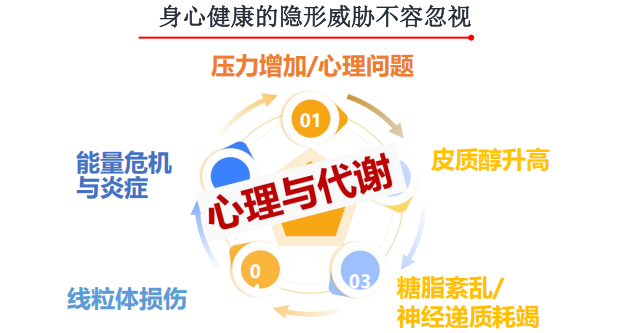

希望之光在行动|青春期叛逆遇上代谢警报:青少年健康筛查为何重要

小明曾经是个爱笑、成绩优异的孩子。但进入初二后,他的成绩突然下滑,晚上做作业的时间越来越长,注意力却越来越差。